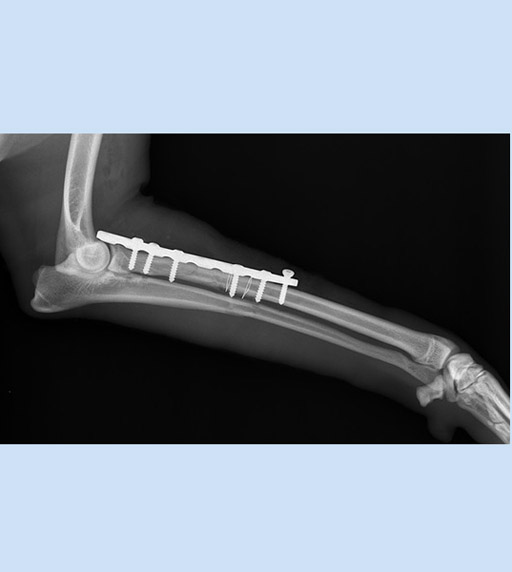

Пластины для остеосинтеза (для животных)Пластины применяются для фиксации переломов костей верхней и нижней конечностей